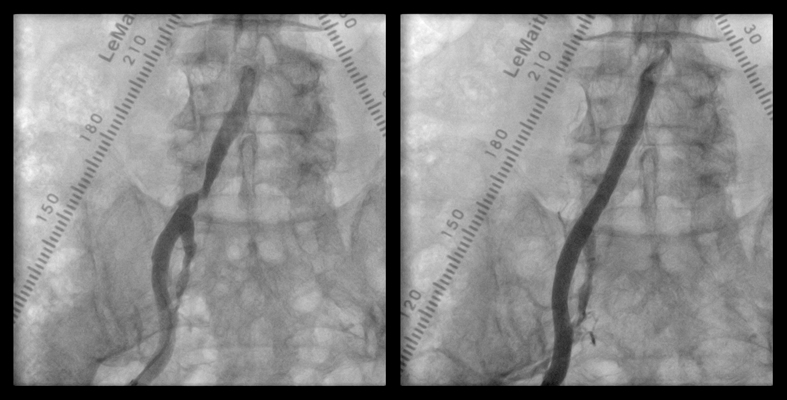

- 浅大腿動脈狭窄 【写真】

- 浅大腿動脈閉塞 【写真】

考え方としては、早期であるほど2の血管内手術のみで治る可能性が高いと考えてよいでしょう。現在の末梢動脈に対する血管内手術の適応は、大動脈・腸骨動脈領域から膝下動脈、さらに足関節から足趾にまで及びます。しかし、それぞれの治療法には当然ながら適応があります。このためしばしば従来からの手術との組み合わせであるハイブリッド手術が必要になりますが、血管内呪術の関与する割合は8~9割にも及んでいます。